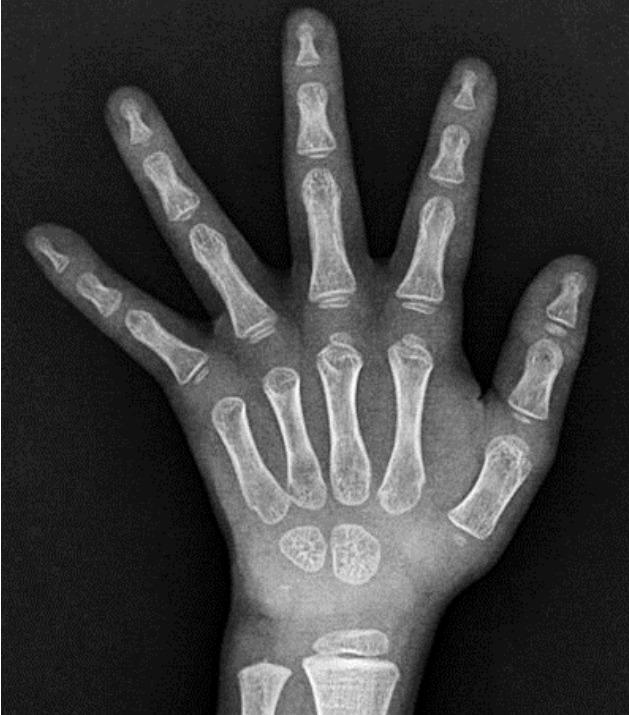

Thyroid hormone resistance (RTH) is characterized by a decreased sensitivity of target tissues to thyroid hormones due to a defect in the THRα- and THRβ-encoded thyroid hormone receptors (THRs). The clinical manifestations range from no symptoms to simple goiter and hypo- or hyperthyroidism, depending on the receptor subtype distribution in the tissues. Here, we report the case of a thyroid hormone-resistant 12-month-old boy carrying a novel THRβ variant who was initially diagnosed with congenital hypothyroidism. An extensive evaluation revealed increased free T4 level and inappropriately increased thyroid-stimulating hormone (TSH) level; a normal lipid profile, sex hormone-binding globulin, and free alpha subunit of TSH; exaggerated TSH response to THR; and no radiological evidence of pituitary adenoma. A targeted next-generation sequencing panel identified a heterozygote c.993T>G (p.Asn331Lys) mutation in the THRβ gene. During the first year of life, a higher dose of levothyroxine was administered to the patient due to uncompensated RTH. Levothyroxine treatment was continued after 3 years to maintain TSH level <5 mIU/mL, but the observed weight gain was poor, height increase was insufficient, and bone development was delayed. However, neither hyperactivity nor developmental delay was observed. Patients with RTH exhibit various clinical features. Due to its heterogeneous nature, genetic test for accurate diagnosis is important to provide proper management.

甲状腺激素抵抗(RTH)的特征是由于编码甲状腺激素受体(THRs)的THRα和THRβ存在缺陷,导致靶组织对甲状腺激素的敏感性降低。临床表现从无症状到单纯性甲状腺肿以及甲状腺功能减退或亢进不等,这取决于组织中受体亚型的分布。在此,我们报告一例携带新型THRβ变异体的12个月大甲状腺激素抵抗男孩的病例,该男孩最初被诊断为先天性甲状腺功能减退。全面评估显示游离T4水平升高,促甲状腺激素(TSH)水平异常升高;血脂谱、性激素结合球蛋白和TSH游离α亚基正常;TSH对TRH的反应增强;且无垂体腺瘤的影像学证据。靶向二代测序 panel 鉴定出THRβ基因存在杂合子c.993T>G(p.Asn331Lys)突变。在生命的第一年,由于未代偿的RTH,给患者使用了更高剂量的左甲状腺素。3年后继续进行左甲状腺素治疗以维持TSH水平<5 mIU/mL,但观察到体重增加不佳,身高增长不足,骨骼发育延迟。然而,未观察到多动或发育迟缓。RTH患者表现出各种临床特征。由于其异质性,进行基因检测以准确诊断对于提供适当的管理很重要。